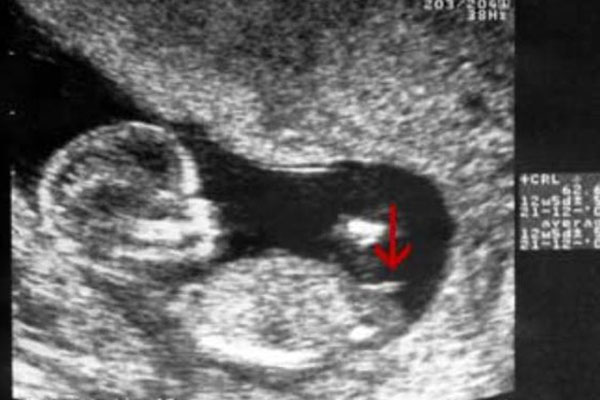

其实,nt报告纸也就是我们说的nt单子,一般做完产检之后都会有这样的一个报告单子,上面有关于本次产检的详细数据,胎儿发育的各项指标等,有的则配有图片,nt检查亦是如此。在nt单子上,最明显的几个胎儿发育数据就有nt厚度值、羊水深度、胎心心率等,上面还有一张放大的胎儿侧面截图,而nt值和nt图就是很明显的男女暗示。

nt图看男女:通过nt图辨别男女就要简单得多了,据说nt图弯着的是男孩,nt图平行的是女孩,这个结论的判断依据就在于脊柱线和尾椎骨。脊柱线受大于角的影响,有的会大于30度或以上,这样看起来就是弯着的。其次就是尾椎骨,一般男孩的尾椎骨才会上翘,这是因为还要发育生殖器的原因,这个上翘姿势是在留下发育空间。